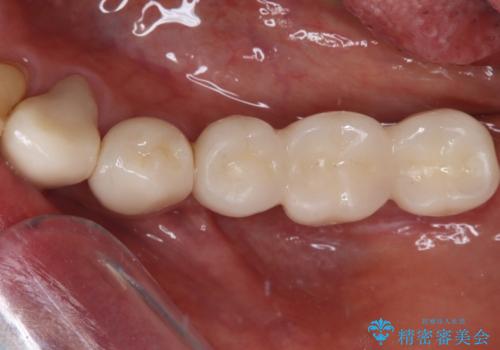

当初は前歯6歯をオールセラミッククラウンで補綴する予定でしたが、前歯が綺麗に仕上がったことで、奥歯まで延長して補綴することとしました。

黄ばんだ前歯や白すぎたクラウン、プラスチックの継ぎ接ぎなどを全てオールセラミッククラウンの統一感のある前歯に仕上げました。